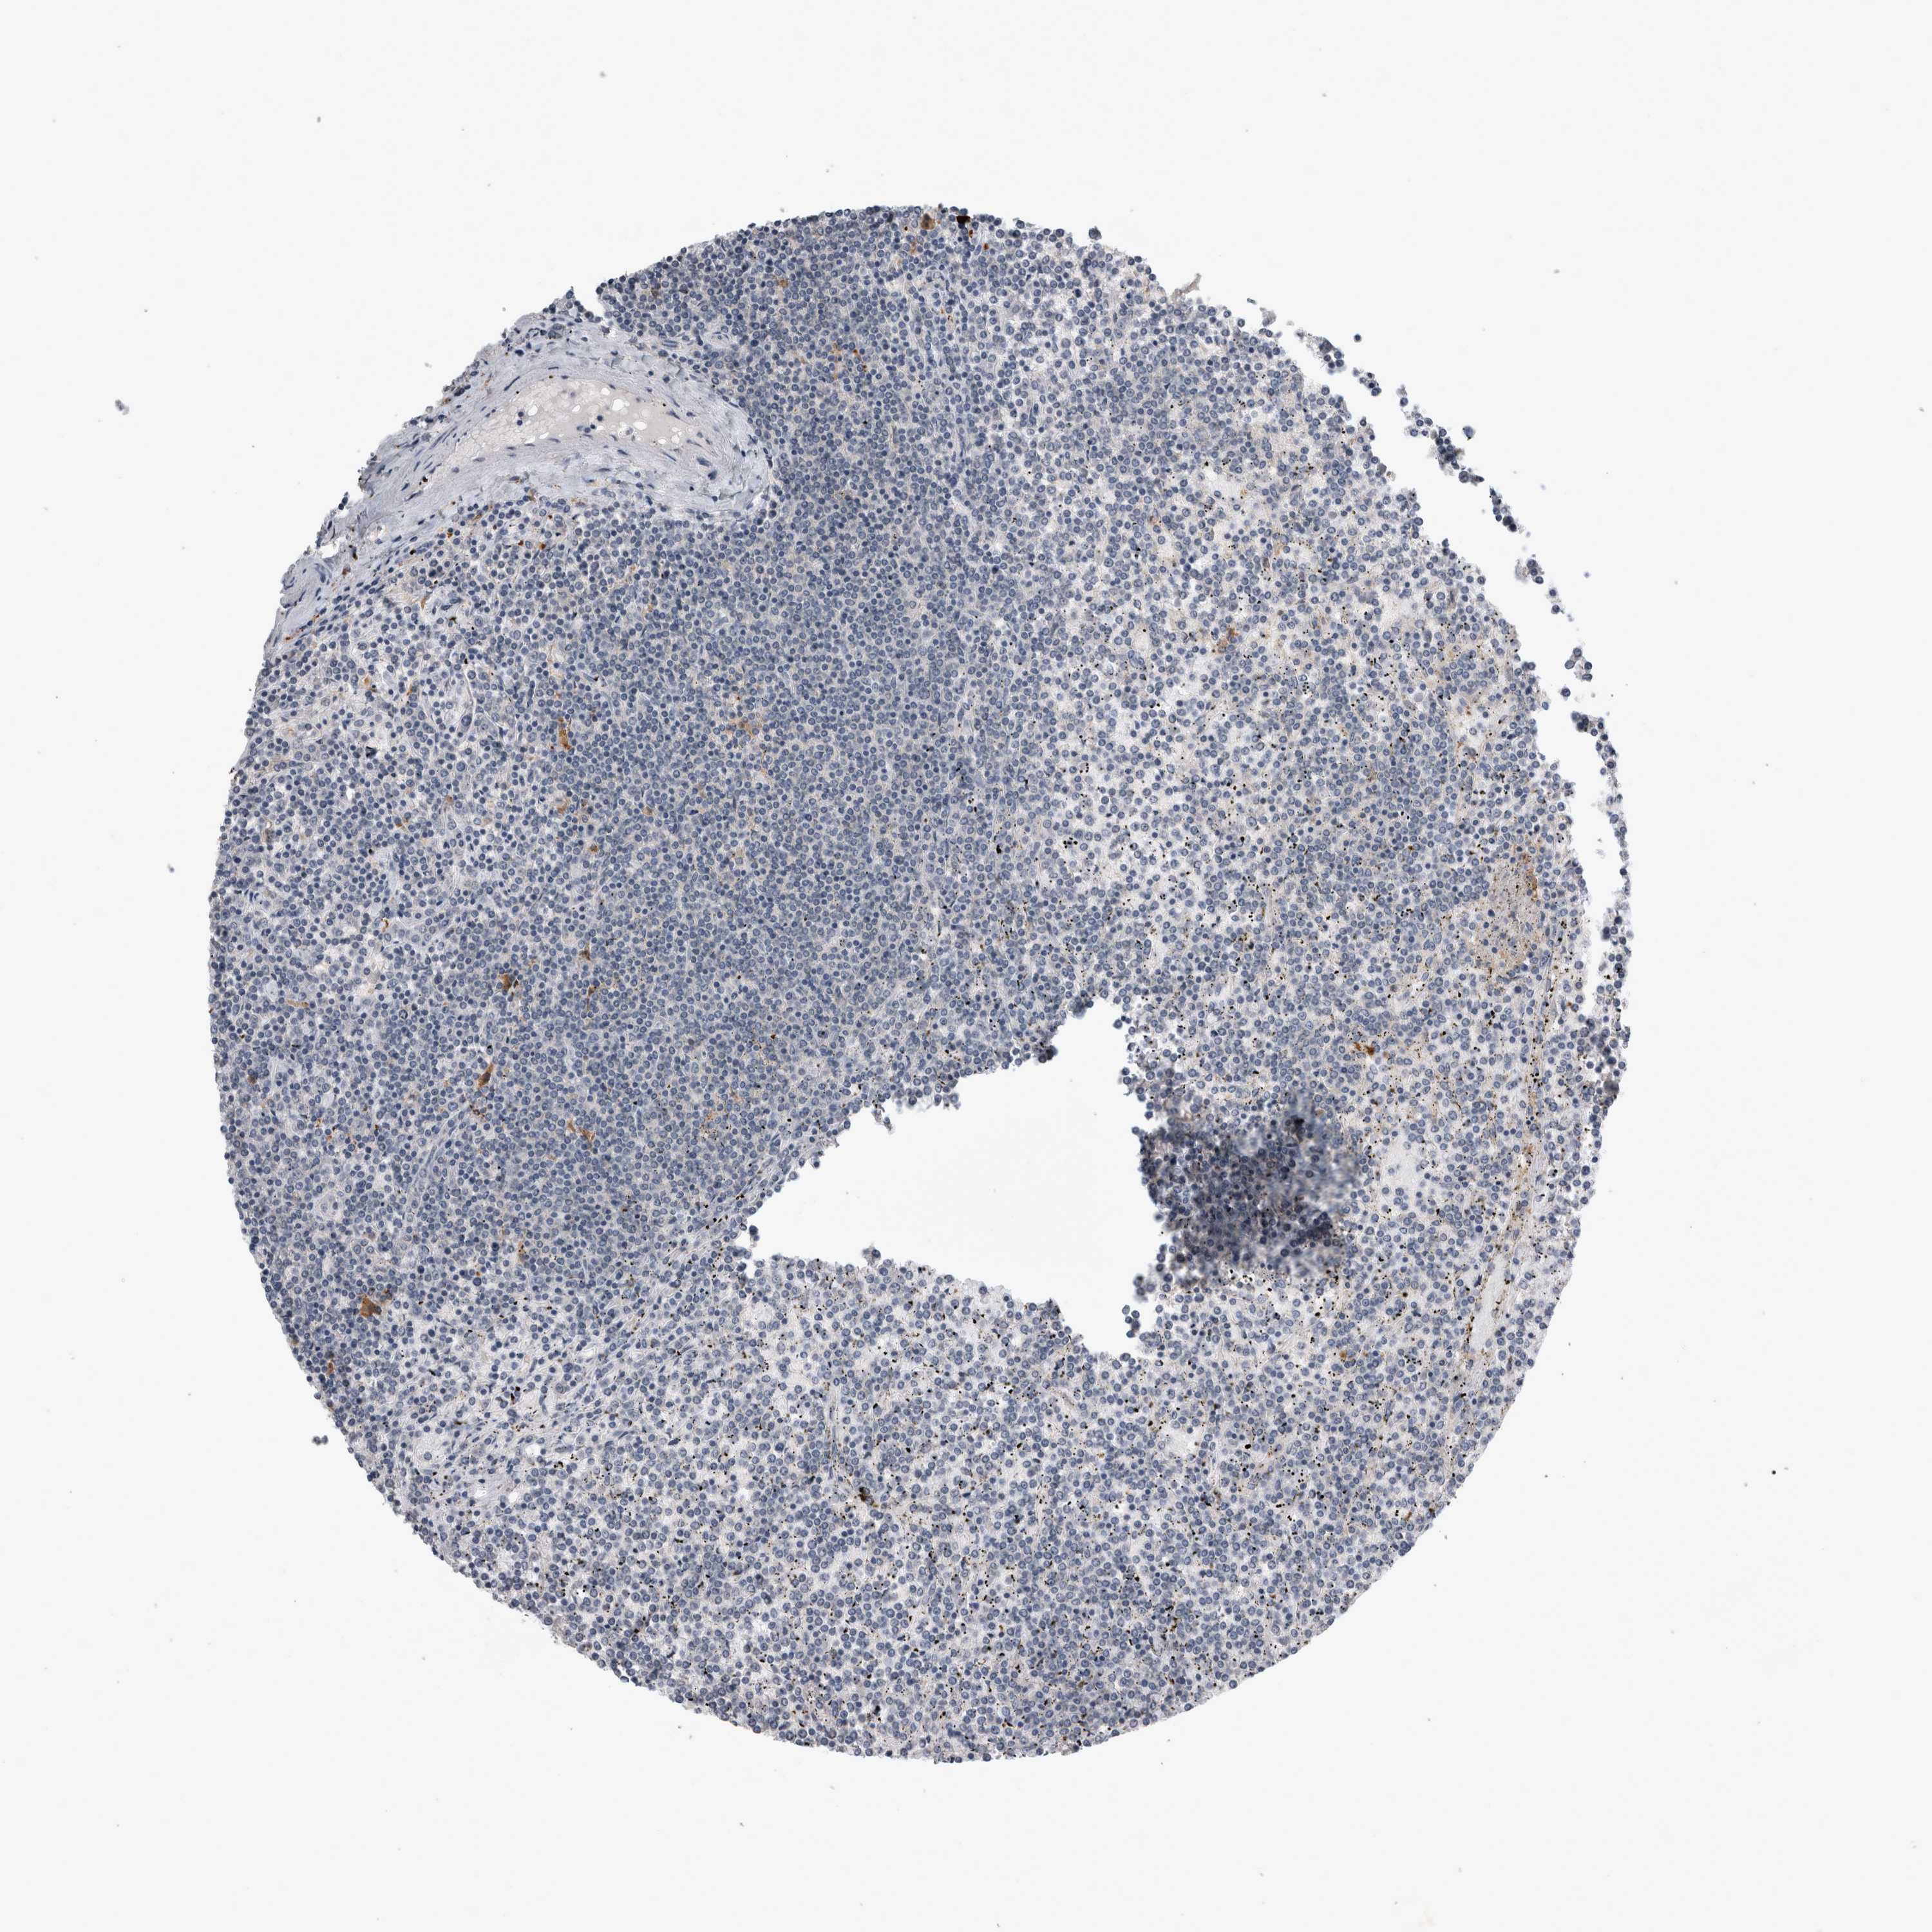

CANCER LYMPHOMA Show tissue menu

LYMPHOMA - Protein expressioni

A mouse-over function shows sample information and annotation data. Click on an image to view it in a full screen mode. Samples can be filtered based on level of antibody staining by selecting one or several of the following categories: high, medium, low and not detected. The assay and annotation is described here.

Each image is clickable and will lead to virtual microscopy that enables deeper exploration of all samples and also displays staining intensity scores, fraction scores and subcellular localization as well as patient and tissue information for each sample.

Antibody HPA026076

Staining

High

Medium

Low

Not detected

Intensity

Strong

Moderate

Weak

Negative

Quantity

>75%

75%-25%

<25%

None

Location

Nuclear

Cytoplasmic/membranous

Cytoplasmic/membranous,nuclear

Hodgkin's disease, NOS

Malignant lymphoma, non-Hodgkin's type, High grade

Malignant lymphoma, non-Hodgkin's type, Low grade